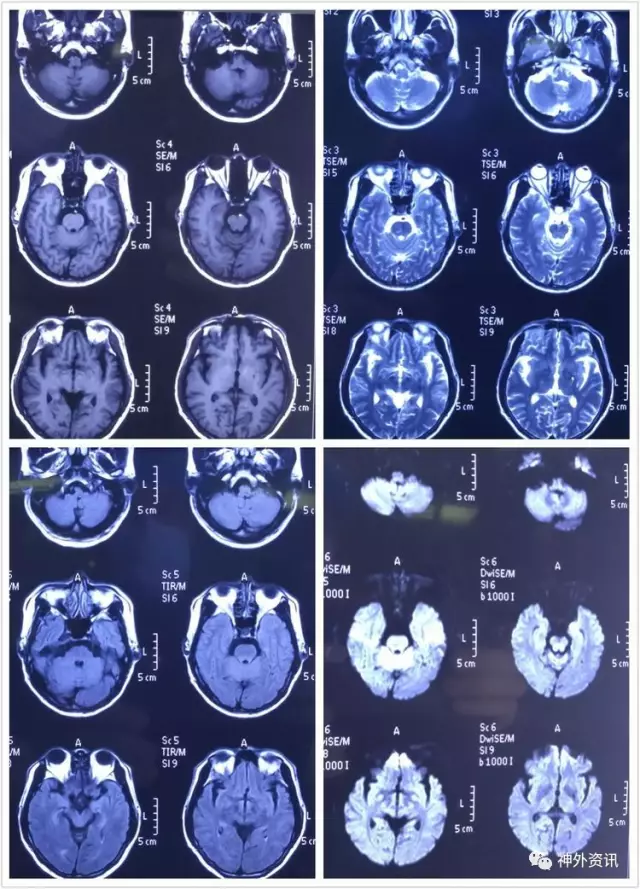

病人MR各成像序列未发现延髓及椎基底动脉供血区新发梗塞,病人应为后循环低灌注状态,具体而言是AICA/pICA缺血表现

该病例请国内脑缺血大咖焦力群主任审阅,焦主任的问题是为什么右椎A优势左椎A狭窄闭塞后有症状,已知的影像学解释是左椎A发出PⅠCA供血双侧,右椎A正位同侧PⅠCA/AlCA均未见显影。